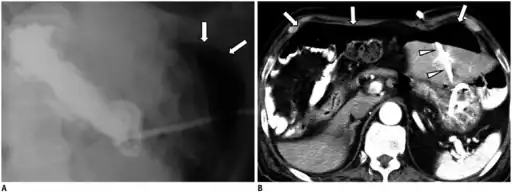

a.b)Pneumoperitoneum developed three days following percutaneous radiologic gastrostomy